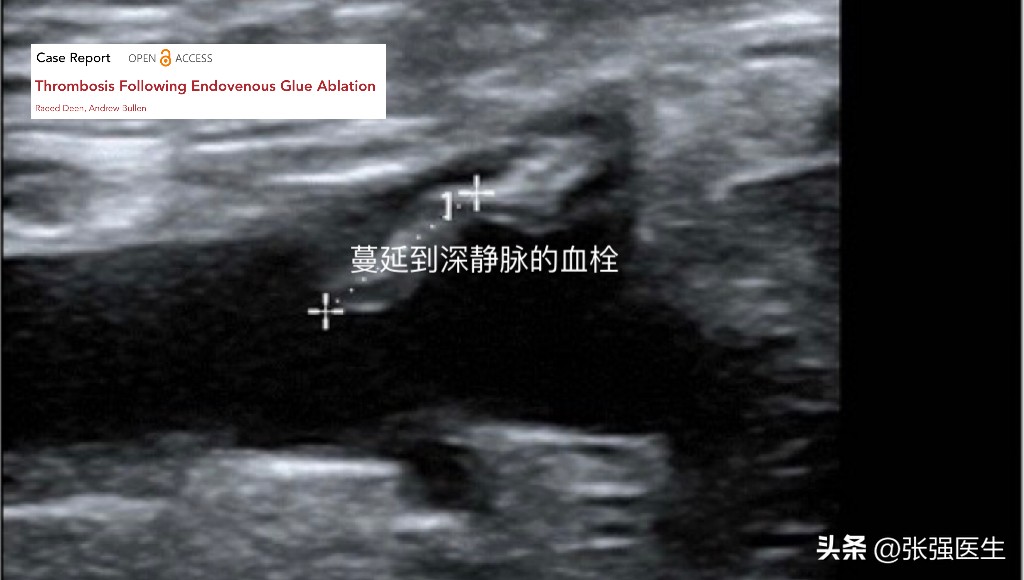

胶合剂引发的深静脉血栓并不常见,往往与操作技术有关。导管位置从初期的距离隐股静脉交界2公分延长到5公分后,深静脉血栓的发生率明显降低。